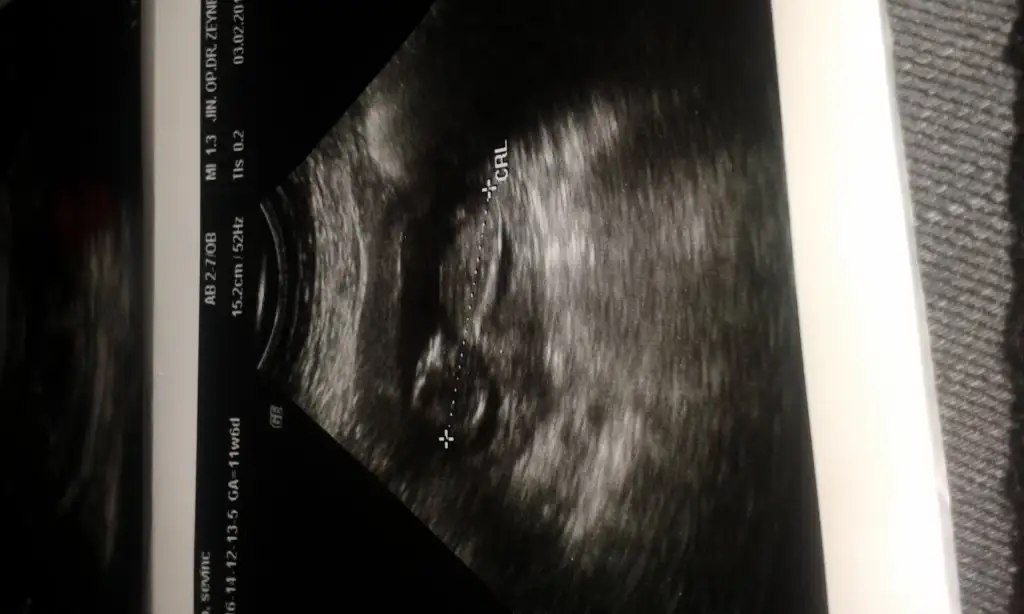

kızlar benim bebeğiminde cinsiyetini tahmin edebilirmisiniz?:KK68:

• 20150302_123817[1].webp

20150302_123817[1].webp

• 20150203_164913[1].webp

20150203_164913[1].webp